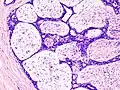

| Histopathologic image of breast fibroadenoma. Core needle biopsy. H&E stain. | |

Histopathologic image of breast fibroadenoma. Core needle biopsy. Hematoxylin & eosin stain. -

Histopathologic image of breast fibroadenoma showing proliferation of intralobular stroma compressing and distorting the epithelium. H&E stain. -